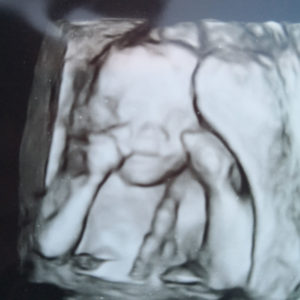

Pregnant After Reversing Rings: Consider A Personal Choice

reversing-tubal-rings-a-personal-choiceThank you so much Dr. Monteith and staff for giving us this opportunity.

I am so thankful that I choose Dr. Monteith to do my tubal reversal!

I would recommend anyone who is thinking of having a tubal reversal to consider A Personal Choice.

Due date 3-22-18!

Patient age: 31

Tubal ligation type: Tubal rings (bands)

Patient hometown: Las Vegas, Nevada